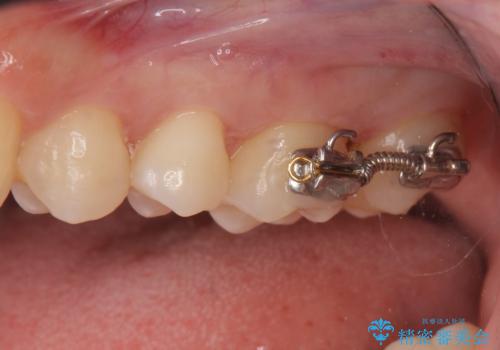

インレーでの修復予定でしたが、歯と歯の間が狭く、正確な型取りが難しい状態でした。

そこで、部分矯正を行い、歯の間を広げてしっかりした歯型を取りました。

広げた期間は2週間ほどです。